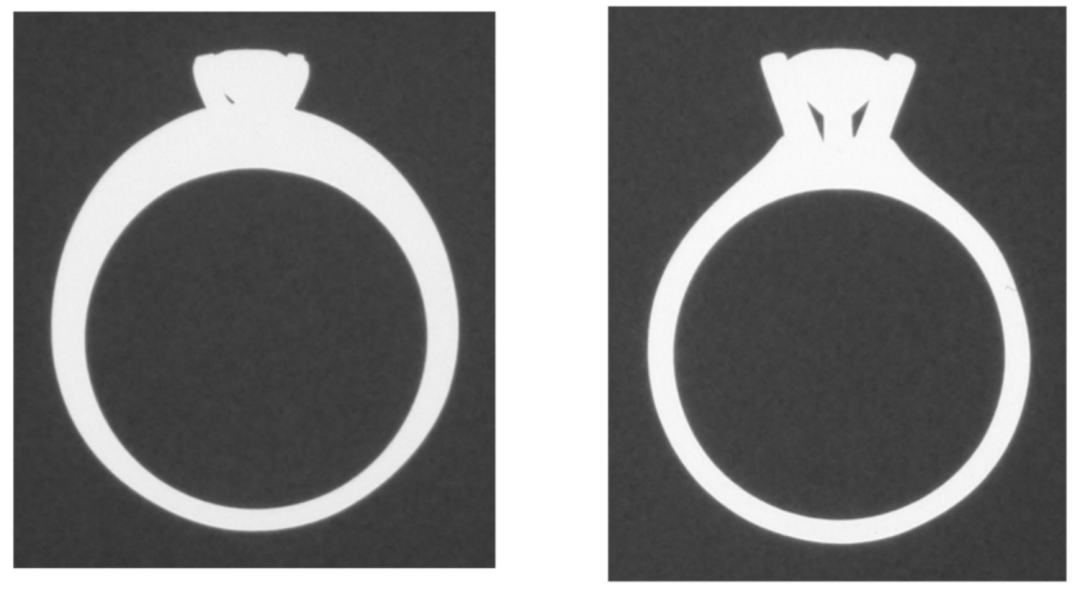

一项研究对经过认证的天然钻石戒指和立方氧化锆晶体做的“钻石”戒指在相同曝光参数下进行成像。

天然钻石戒指的X线照片如(图2)所示,而立方氧化锆晶体仿制的“钻石”戒指的射线照片如(图3)所示。

• 天然钻石始终比立方氧化锆晶体具有更高的射线可透性,表现为低密度。

• 钻石由原子序数为6的碳制构成,其密度与人体组织非常相似,而立方氧化锆的密度与戒指周围的金属一样。

图3. 立方氧化锆晶体仿制的“钻石”戒指在X线下的表现